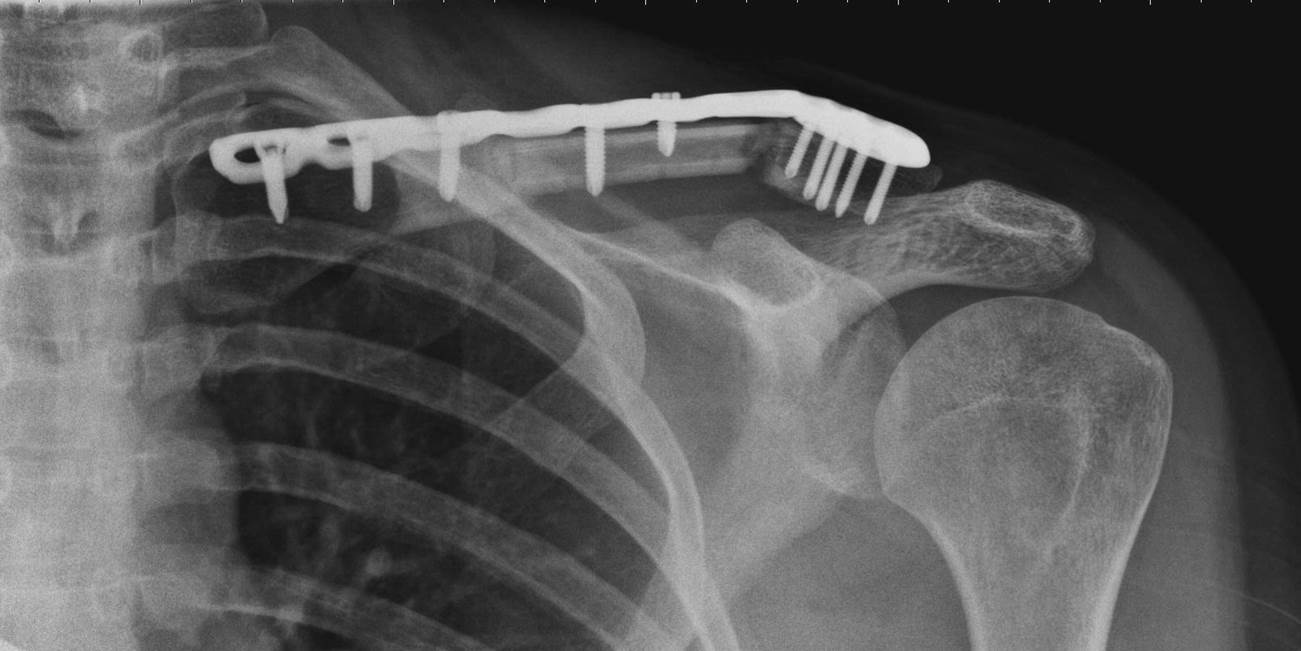

Рис.1. Пациентка, 31 год. Атрофический ложный сустав средней трети левой ключицы, Перелом пластины после костной аутопластики, остеосинтеза пластиной по поводу ложного сустава.

Рис.2. Пациентка, 31 год. 3 месяца после операции. Срастающаяся левая ключица после разрушения ложного сустава, костной пластики свободным кровоснабжаемым аутотрансплантатом, фиксации костных отломков пластиной и винтами. Рис.3. Пациентка, 31 год. 12 месяцев после операции. Срастающаяся левая ключица после разрушения ложного сустава, костной пластики свободным кровоснабжаемым аутотрансплантатом, фиксации костных отломков пластиной и винтами